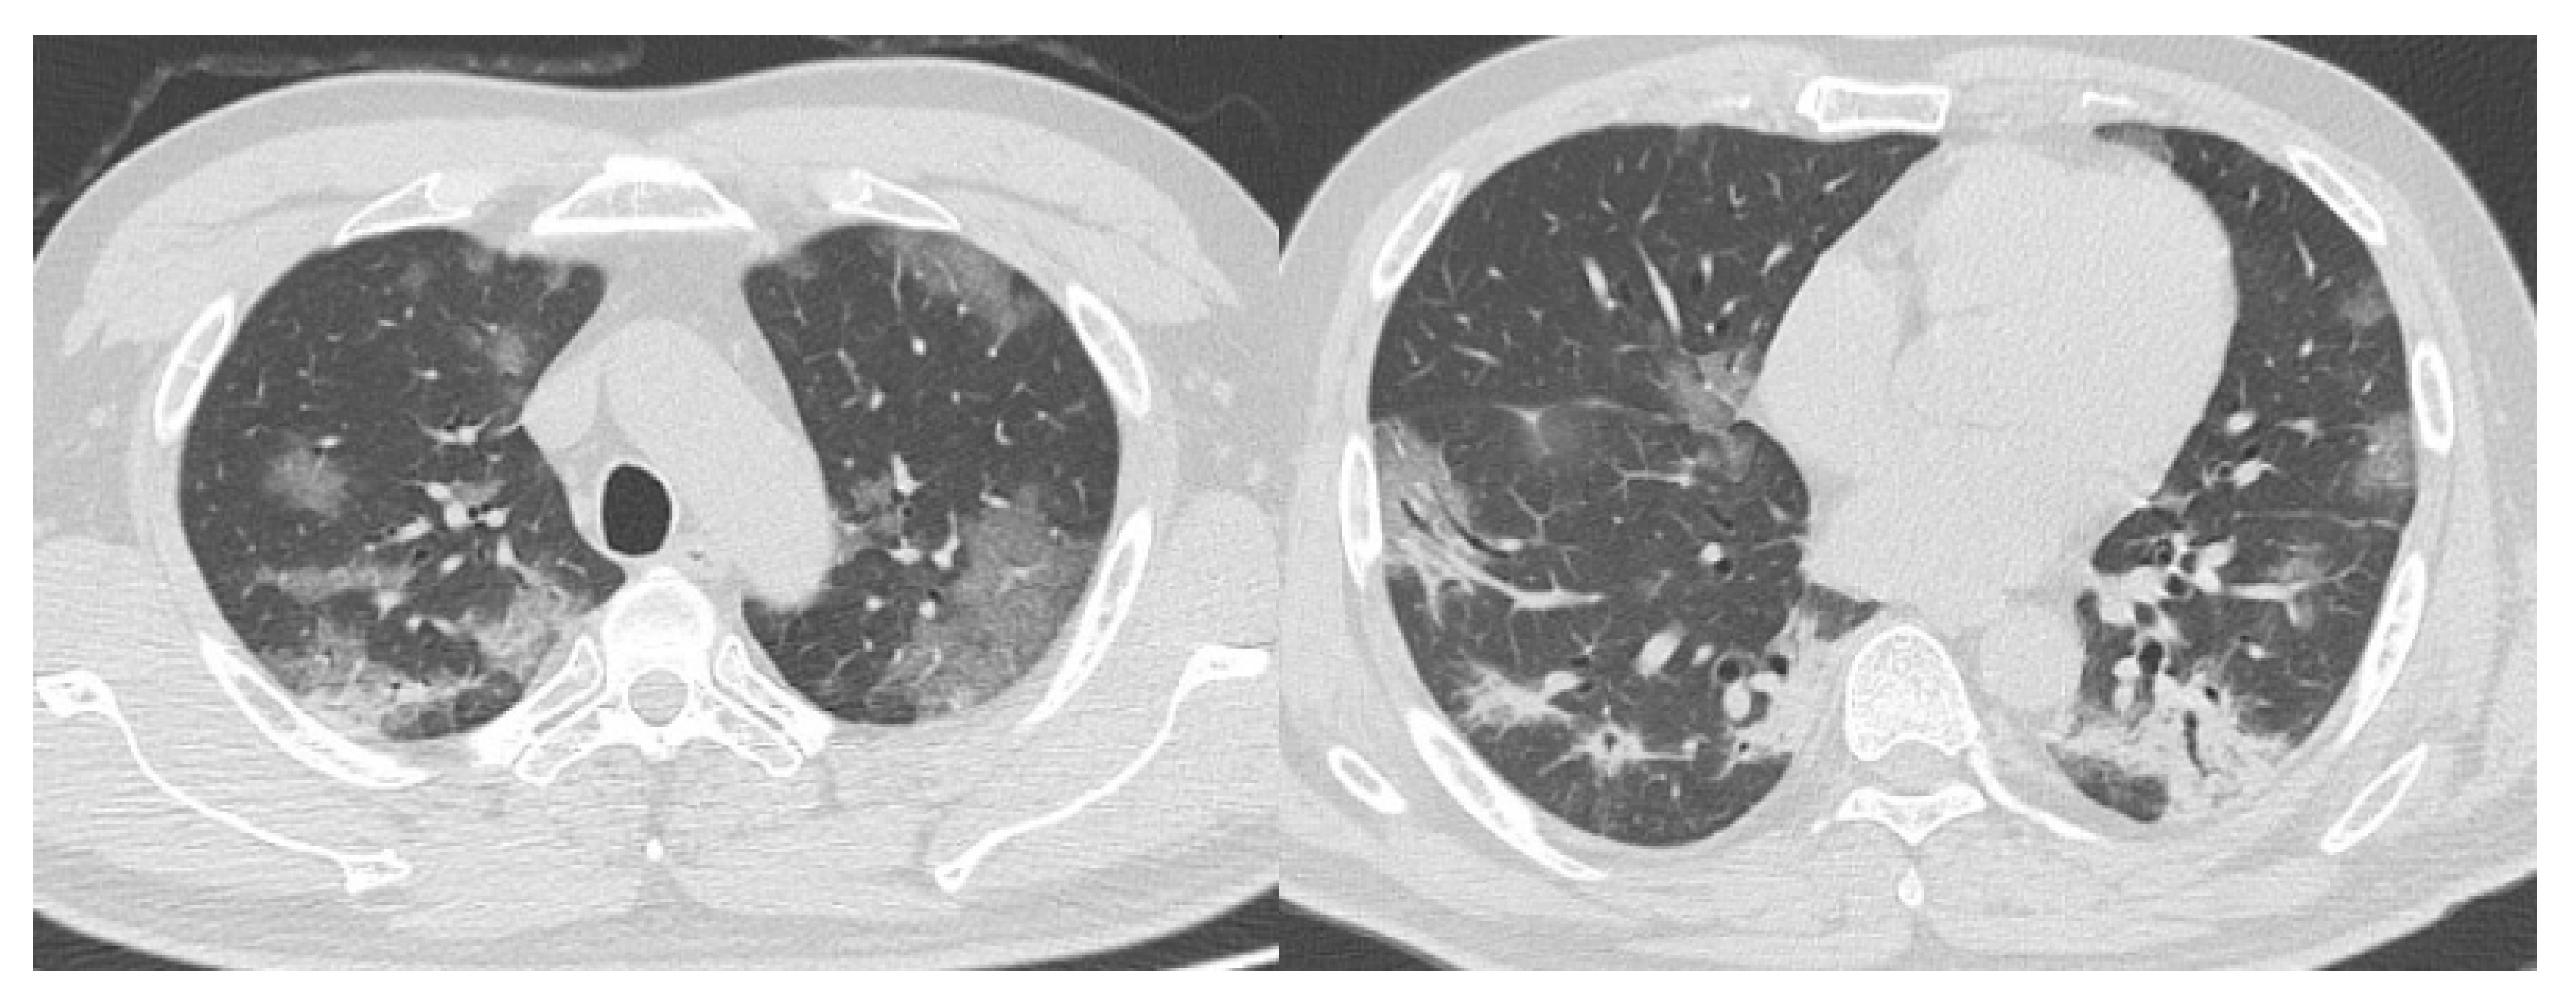

- CO-RADS 2 means a low level of suspicion for pulmonary lesion resulting from COVID-19, based on CT findings in the lungs typical of etiology indicative of infections other than COVID-19, including bronchitis, infectious bronchiolitis, bronchopneumonia, lobar pneumonia, and pulmonary abscess. Findings include a tree-in-bud sign, a centrilobular nodular pattern, lobar or segmental consolidation, and lung cavitation.

- CO-RADS 3 means CT findings equivocal for pulmonary involvement of COVID-19 that can also be seen in other types of viral pneumonia or non-infectious etiologies. Findings include perihilar ground-glass, homogenous extensive ground-glass with or without sparing of some secondary pulmonary lobules, or ground-glass together with smooth interlobular septal thickening with or without pleural effusion in the absence of other typical CT findings.

- CO-RADS 4 means a high level of suspicion for pulmonary lesion resulting from COVID-19, based on typical CT findings but exhibiting some overlap with other types of (viral) pneumonia. Findings are not located in contact with the visceral pleura or are located strictly unilaterally, have a predominantly peribronchial distribution, or overlap with severe diffuse preexisting pulmonary abnormalities.

- CO-RADS 5 means a very high level of suspicion for pulmonary lesion resulting from COVID-19, based on typical CT findings. Obligatory features are ground-glass opacities, with or without consolidations, close to visceral pleural surfaces, including the fissures, and a multifocal bilateral distribution.